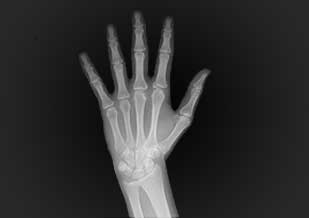

Radiografía carpal

Es una radiografía que es para estimar la edad ósea y comprarla con la edad cronológica. Usada en odontopediatría, ortodoncia, odontología legal y forense.